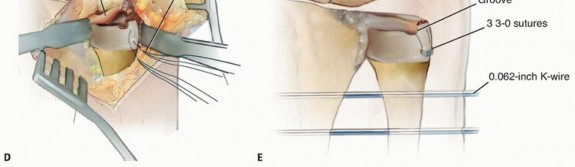

Open Reduction Distal Radioulnar Joint and Triangular Fibrocartilage Complex Open Repair Indicated in the treatment of the irreducible DRUJ following radial fixation If the DRUJ remains irreducible after anatomic reduction of the radial shaft fracture, soft tissue interposition is suspected. Open reduction to remove interposed soft tissue and TFCC repair should be performed.10 The following description assumes the native anatomy is not disrupted. Unfortunately, if this approach is being made for an irreducible DRUJ, there will be disrupted tissue planes as a result of interposed structures, capsular tears, etc. It is important to be able to identify the structures and attempt to restore them to their native positions, stabilizing them with tissue repair after joint reduction. A 2- to 3-cm gently curved dorsal longitudinal incision is made over the distal ulna, and blunt dissection is performed through the subcutaneous tissue, cauterizing small vessels with bipolar cautery (TECH FIG 2A). The dorsal cutaneous branch of the ulnar nerve is identified and care is taken throughout the procedure to protect it. A longitudinal incision is made through the thin extensor retinaculum between the fourth and fifth extensor compartments (TECH FIG 2B).3 Avoid amputating the flap during radial to ulnar elevation. Avoid violation of the ECU subsheath. The extensor digiti quinti (EDQ) is released from the fifth compartment and retracted radially. An ulnar-based capsulotomy is made (TECH FIG 2C). The distal transverse limb is made at the level of the palpable triquetrum, proceeding in an ulnar to radial direction along the dorsal radiocarpal ligament, from the ECU tendon to the floor of the fifth compartment. The capsulotomy is then continued proximally in a longitudinal fashion through the floor of the fifth compartment to the level of the ulnar neck. Care needs to be taken not to cut through the dorsal radioulnar ligament of the triangular fibrocartilage (TFC). Small double skin hooks placing tension on the capsular flap will assists in avoiding injury to the underlying TFC. Finally, the proximal transverse capsulotomy is made across the ulnar neck to ECU tendon. If needed for visualization and working space, the ulnomeniscal homolog, which extends distal from the TFC into the ulnocarpal joint, can be excised. Bipolar cautery may be needed for hemostasis following its excision.3 The key to the entire dissection is to create clean planes that sharply define the structures, allowing them to be repaired during layered closure. Next, a small curette is used to create a small trough in the ulna fovea exposing cancellous bone.

TECH FIG 2 • Open DRUJ/TFCC exposure and repair. A. Incision. B. Extensor retinaculum opened exposing fifth compartment. C. TFCC and DRUJ exposed. D. 3-0 nonabsorbable sutures placed through TFCC and ulna bone tunnels. E. Final construct demonstrating transfixation with 0.062-inch K-wires and TFCC repair. A 0.045-inch smooth stainless steel pin is used to drill two bone tunnels, separated by a 1-cm bony bridge, from the medial ulna to the ulnar fovea. Next, three 3-0 braided nonabsorbable suture are passed one at time through one of the bone tunnels, through the TFC, and back out the other bone tunnel (outside-in to inside-out) (TECH FIG 2D).9 Prior to tying the sutures, the DRUJ is reduced and pinned with two 1.6- or 2-mm smooth stainless steel pins as previously described. Finally, the sutures are tied down over the ulna. A layer-by-layer closure is performed. The dorsal radioulnar ligament of the TFC can be sutured back to the capsule during closure (TECH FIG 2E).